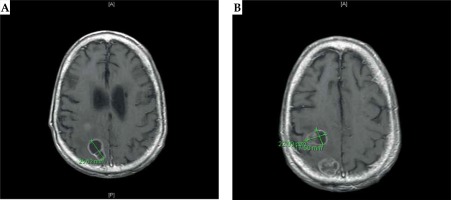

The patient, a 57-year-old male with a history of stage IV hypopharyngeal cancer, who was treated with chemotherapy and external beam radiation (70 Gy) to the neck in 2012. Two years later, the patient presented with a headache and was found to have a 1.5 cm left parietal lobe metastasis, which was treated with linac-based SRS to 20 Gy prescribed to an 80% isodose line on April 7th, 2015. Preoperative MRI on April 9th, 2015 revealed two metastases in the right frontal lobe and the right parietal lobe 1.9 cm × 2.3 cm × 2.4 cm and 2.7 cm × 2.2 cm × 2.9 cm, respectively (Figure 1). On April 10th, 2015, the patient had both the right frontal and right parietal lesions treated with one right frontoparietal craniotomy and with the immediate intraoperative placement of 131Cs brachytherapy. A gross total resection of both tumors was achieved, which combined to form one large cavity (over 5.3 cm total maximal preoperative tumor diameter). Minimal brain tissue was removed between the lesions, representing a total volume of approximately 0.5 cm × 0.3 cm × 0.4 cm. A total of twenty-six 131Cs stranded seeds with activity of 3.76 mCi were implanted, with a dose of 80 Gy to a depth of 5 mm from the perimeter of the cavity, using the technique described in our original published phase I/II trial [13]. We used preoperative magnetic resonance imaging (MRI) scans as well as our institutional physics nomogram to calculate the dose of the volume implant. This was adjusted intraoperatively for the change in intracavitary volume after resection of the tumor. The 10 cm, suture-stranded 131Cs seeds (0.5 cm inter-seed spacing) were delivered in strings of 10 seeds per string, subsequently cut into smaller lengths per the nomogram, and placed as a permanent volume implant along the cavity in a tangential pattern to maintain a 7 to 10 mm spacing between seeds. As a result, the combined cavity was lined with the seeds in a pattern like barrel staves or parallel tracks (Figure 2A). The 131Cs seeds were stranded and cut in real time in order to accommodate and precisely fit the resected cavity. The seeds were covered with surgicel (Ethicon) to prevent seed migration and alteration of dosimetry (Figure 2B), and tisseel (Baxter) was used to line the cavity to limit cavity shrinkage and further prevent seed dislodgement.

Fig. 1

A) Preoperative MRI of the brain: axial T1-weighted images demonstrate an enhancing anterior posterior right frontal lesion, measuring approximately 1.9 cm × 2.3 cm × 2.4 cm. B) Preoperative MRI of the brain: axial T1-weighted images demonstrate an enhancing posterior right parietal lesion measuring approximately 2.7 cm × 2.2 cm × 2.9 cm